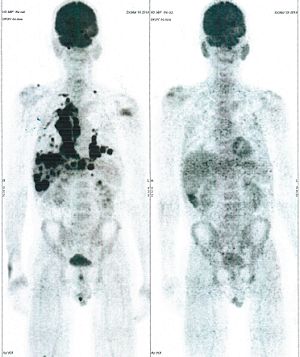

CASE NO: 28 (MASSIVE LIVER METASTASES)

A 50+ woman is very weak and bedridden, with massive liver metastases of unknown origin. After a few treatment, the cancer in the liver has shrunk by more than half, and the women can walk and feels much better. Treatment is continuing. This case illustrates again that it is not necessary to know the histology of the cancer before starting treatment.